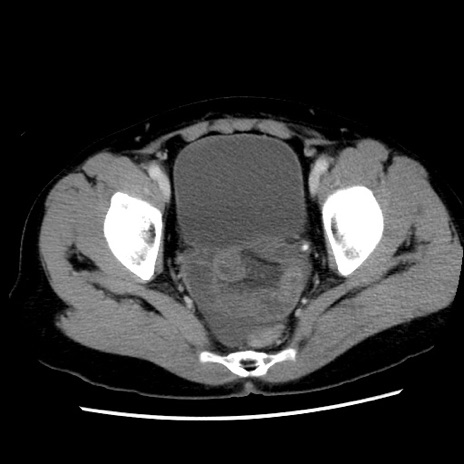

症例10(横断像)

【症例】 50歳代女性

【主訴】 腹痛

【現病歴】前日生レバーを食べた。今朝に排便あり。 昼前に突然発症の腹痛を生じ、当院救急外来を受診した。

【既往歴】 子宮筋腫にてで子宮全摘後

【身体所見】 意識清明、腹部:平坦、軟、下腹部やや左を中心に圧痛・反跳痛あり、筋性防御あり

【データ】WBC 7800、CRP 0.07